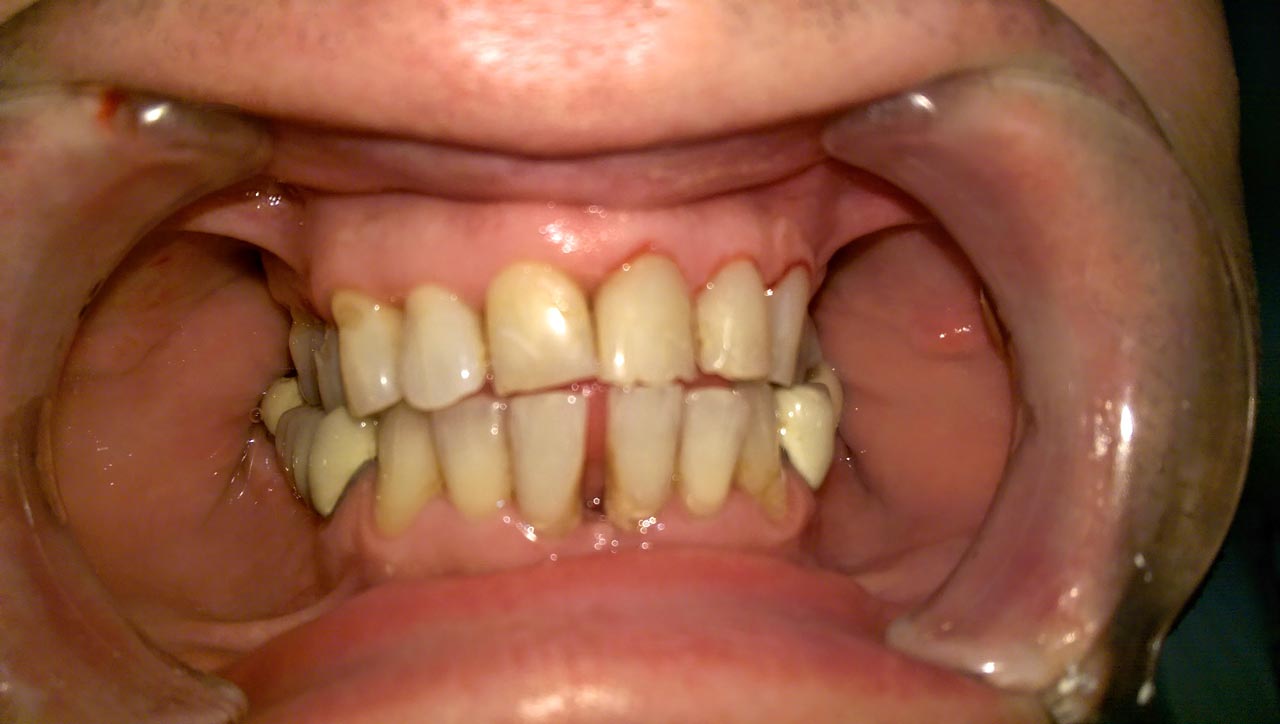

Fogmegtartó kezelések

Amennyiben pácienseink rendszeresen részt vesznek az éves szűrővizsgálaton, az esetek jelentős részében elkerülhetőek a foghúzások, szájsebészeti komolyabb beavatkozások, és csupán apróbb kezelésekre lehet szükség! Ilyenek például a szájhigiéniás kezelések, esztétikus tömések, betétek, koronák, gyökérkezelések.

Betegeink többféle (kémiai kötésű és fényre kötő) esztétikus tömés közül orvosainkkal együtt választják ki a megfelelőbbet! Fémmentes betéteinkkel, koronáinkkal természethűen tudjuk visszaállítani fogazatát. Gyökérkezeléseket csúcstechnológiás gépi tágítóval végezzük, aminek segítségével milliméter pontosan tudjuk bemérni a gyökértöméshez a csatorna hosszát.